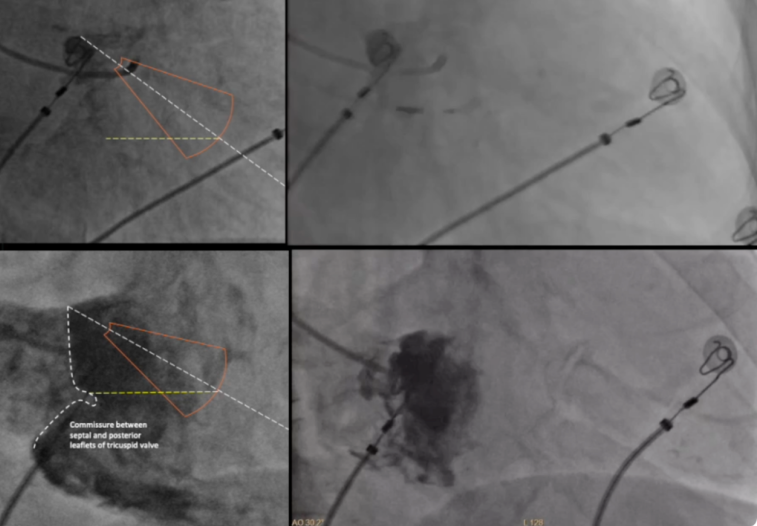

影像指导:RAO 30°下行三尖瓣心室侧造影以明确三尖瓣隔瓣与后瓣关系,以瓣环顶点与心尖之间的连线为轴线,对应三尖瓣隔瓣中-下2/3水平形成的扇形区域作为电极拧入点,逆时针轻微转动C315鞘以指向间隔(图1)。

图1.三尖瓣环造影及拧入点定位